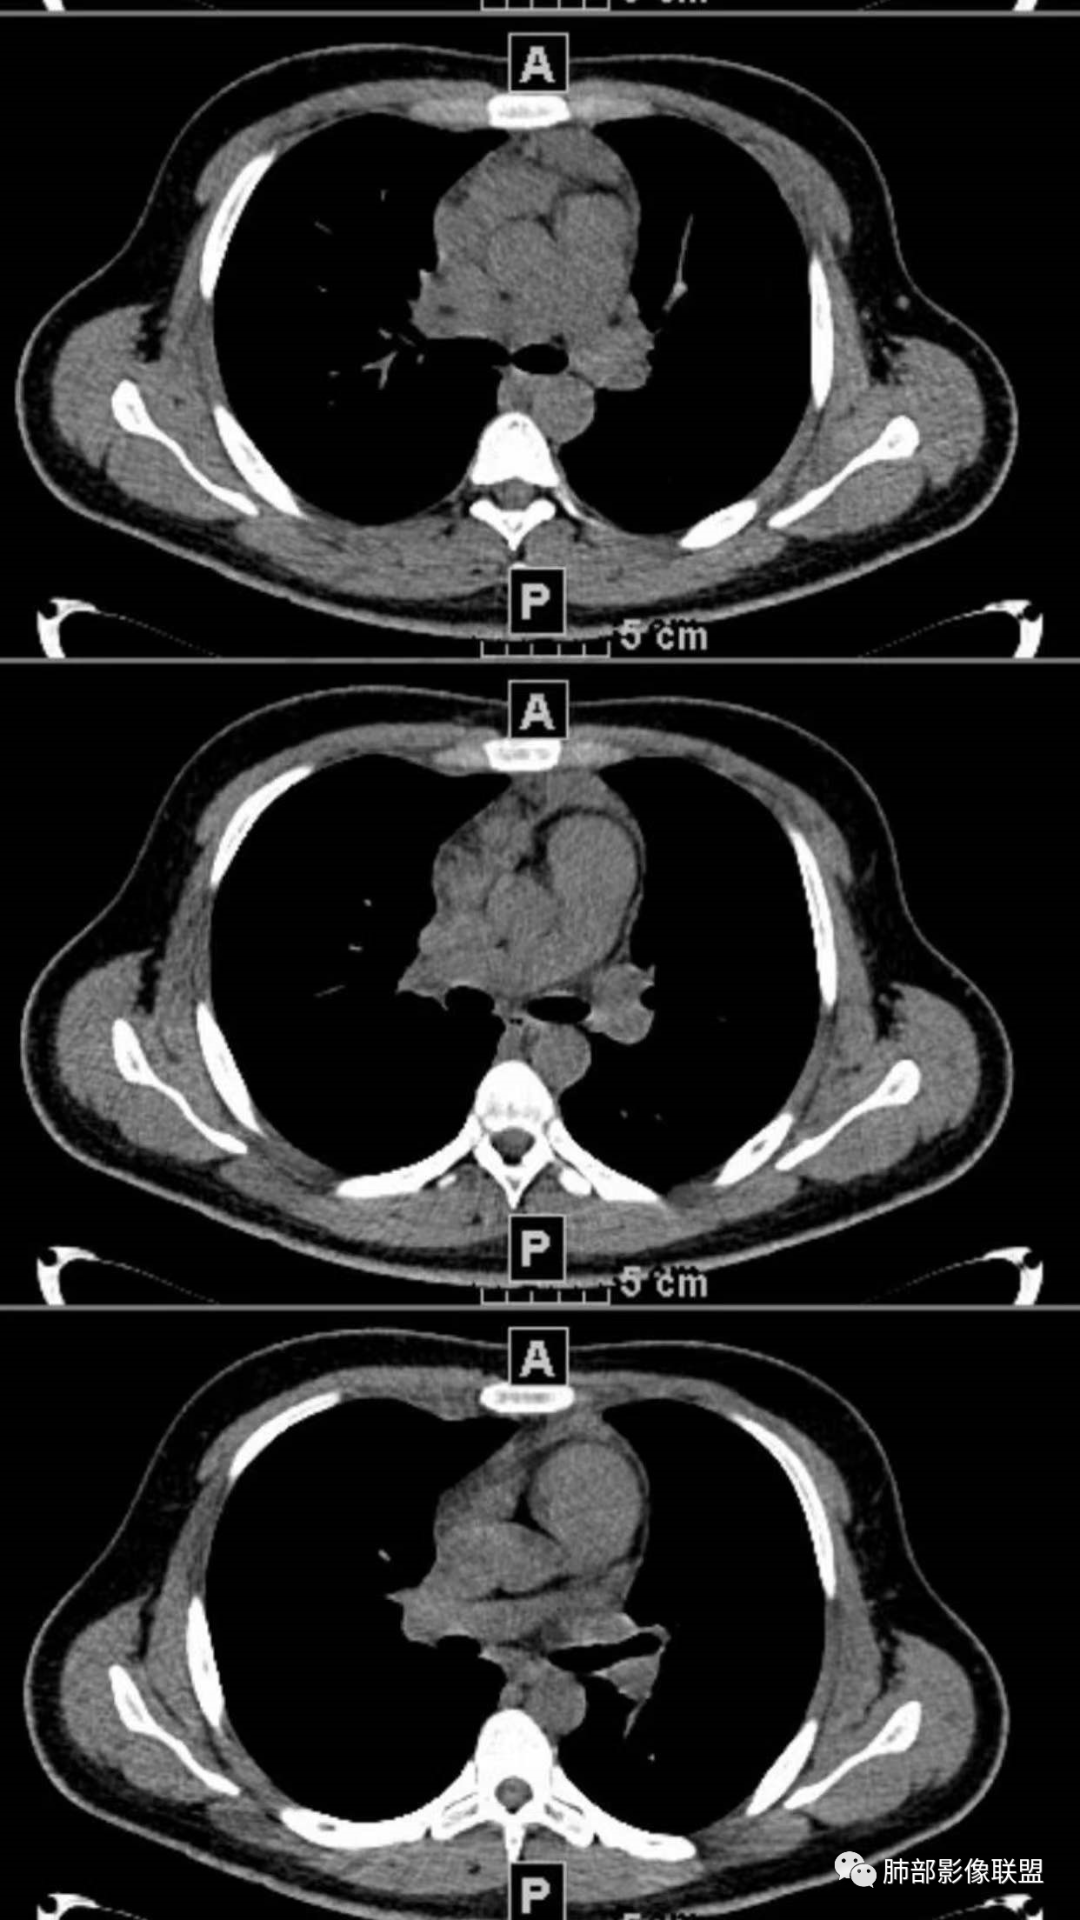

2、影像特点:两肺可见多发大小不一的结节影,部分结节周围可见晕征,部分结节沿着支气管血管束分布,部分位于胸膜下。前纵隔内可见多发结节样软组织密度影,边界不清,部分病灶融合倾向,其脂肪间隙显示模糊。由于腹腔层面少,未能确定腹腔内有无增大淋巴结,需要连续层面追踪观察。

3、病例小结:年轻男性+前纵隔多发结节样软组织影+双肺多发结节,需要警惕淋巴瘤,至于多数老师提到鉴别结节病,结节病以双肺门对称性淋巴结肿大为典型表现,其肺内表现多为沿肺门旁支气管血管周围间质分布的多发结节,结节病可表现纵隔内多发淋巴结肿大、且淋巴结密实,孤立少融合,该病例中均缺乏以上特点,另外结节病好发中青年女性,此病例年龄亦不符合。